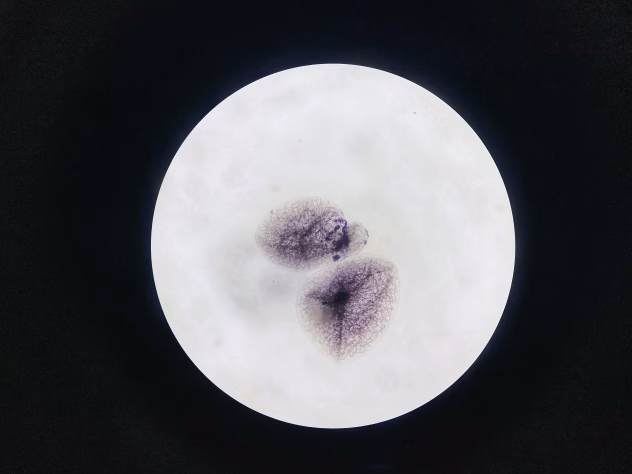

Pastaraisiais metais mokslininkai vis garsiau įspėja apie visame pasaulyje plintančias laisvai gyvenančias amebas. Šie mikroskopiniai organizmai, gyvenantys vandenyje ir dirvožemyje, gali sukelti itin pavojingas, dažnai mirtimi pasibaigiančias infekcijas.

Viena jų – vadinamoji „smegenis ėdanti“ ameba Naegleria fowleri – jau vertinama kaip auganti globali grėsmė ir aktuali rizika ir mūsų regionui. Tyrėjai ragina imtis skubių priemonių dėl vis plačiau paplitusių laisvai gyvenančių amebų – mikroorganizmų, galinčių išgyventi vandenyje ir dirvoje ir keliančių rimtą pavojų žmonių sveikatai.

Ypatingas dėmesys skiriamas Naegleria fowleri, geriau žinomai kaip „smegenis ėdanti ameba“. Laisvai gyvenančios amebos – tai vienaląsčiai organizmai, kuriems nereikia šeimininko. Jos geba keisti savo formą pasitelkdamos išaugas – pseudopodijas, ir aptinkamos įvairiose aplinkose: nuo paprastų balų iki ežerų.

Pavojingiausia iš jų – Naegleria fowleri – labiausiai mėgsta šiltą gėlą vandenį ir dažniausiai randama esant 30–40 °C temperatūrai.